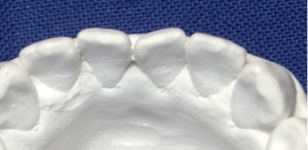

SLAを用いた当院の症例

安定調査症例2

伊藤矯正歯科医院での安定した症例

これに対し伊藤矯正歯科医院では、抜歯を伴う矯正を行ったのちに何も装置を使用しなくて何年か経過しても、かなり安定している症例をみることが多くありました。(「安定調査症例1~4」と当HPの症例集ページ「叢生第3,4症例」をご覧下さい。)そこで治療が終わって数年経過した時点で、資料採得のできた14症例について歯並びの変化を観察しました。